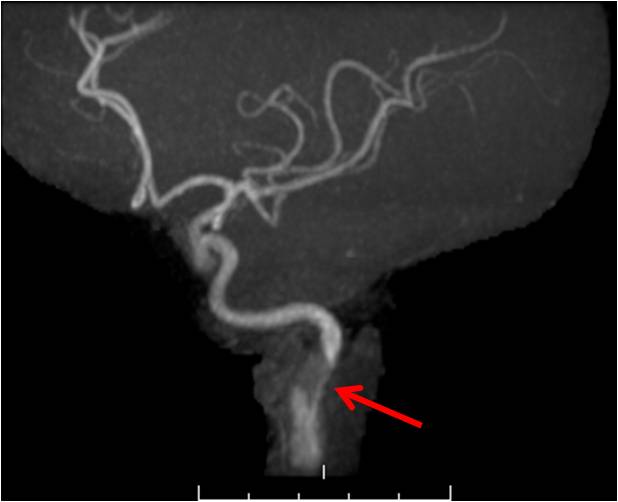

Usually patients who present with otherwise unexplained artery dissection or visceral artery aneurysm will undergo further imaging. This imaging should probably include a CT or MR angiogram of the brain, neck, chest, abdomen and pelvis. The purpose of such imaging is to detect typical disease patterns and also to assess the extent of disease. It is not uncommon for such imaging to result in evidence of dissection in other, asymptomatic, vascular beds. For example, a patient presenting with carotid artery dissection may be found to have renal infarctions she has never known she had and perhaps also even spontaneous coronary artery dissection (SCAD). Patients with fibromuscular dysplasia should be screened for intracranial aneurysms.

A word of caution is important in regards to diagnosing vasculopathies by imaging alone. As mentioned above, as of 2017, vasculopathies other than fibromuscular dysplasia often do not have typical imaging characteristics. Thus, one should be careful when reading a radiology report suggesting one diagnosis over the other. It is my experience that various terms are used loosely and that a vascular specialist with specific knowledge in these diseases should review the images in person.

Even when fibromuscular dysplasia is given as the diagnosis, I have seen many cases when I disagreed. Many colleagues of mine who treat FMD patients have a similar experience. Specifically, it is also important to avoid making a diagnosis based solely on dissected arteries (as a dissection may result in morphological changes in the artery that could result in errors in diagnosis). Thus, another reason to get systemic imaging is to find other, non-dissected, but diseased arteries that can clarify the diagnosis.